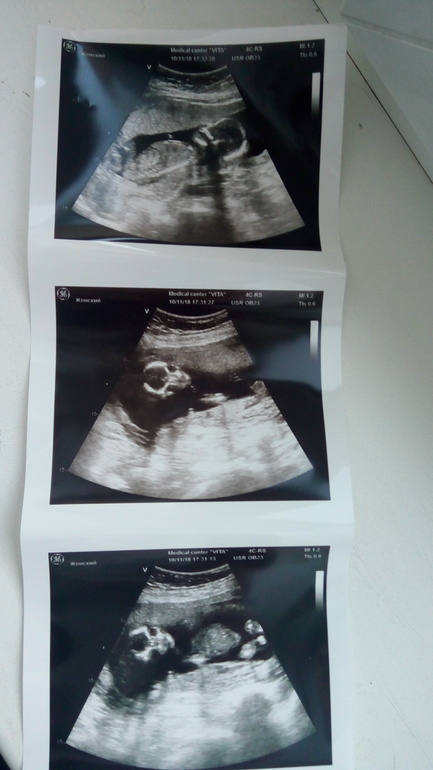

Платный поход на УЗИ

УЗИ, КТГ, доплерНу вот сходили мы с мужем на УЗИ,все показали как и что,походу предполагают уже мальчика,но это не точно,потому что надо было вагинально смотреть,так как лежал попой вниз,но муж сказал что не надо лезть туда ,ну значит точно уже увижу на 20 неделе,спросила по поводу вечерних потягивания внизу живота,прописала магнелис,попробую попить вдруг поможет,говорит что прям тонуса не видит,количество околоплодных вод нормальное,соответствует почти 16 неделям,ну я довольна впринципе и спокойна,буду ждать шевелится и пиночков,хотя шевеления лёгкие бывает чувствую,это точно не кишечник)